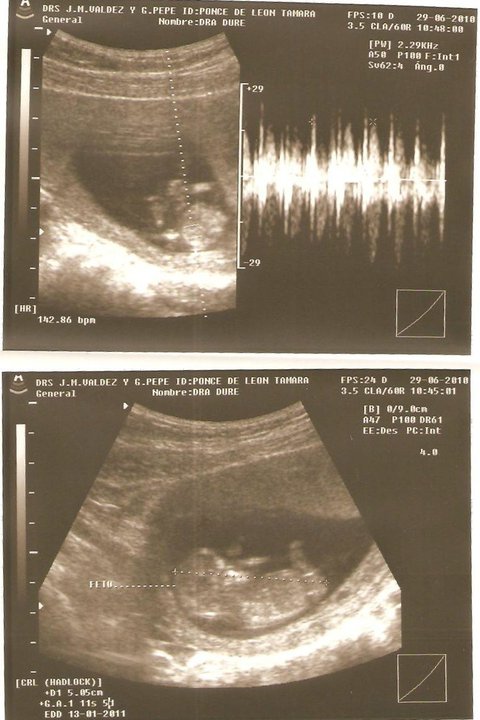

Actividad cardíaca fetal

La identificación de pulsaciones cardíacas fetales separadas y distintas de las de la madre asegura el diagnóstico del embarazo. Se puede auscultar la actividad cardíaca fetal con un estetoscopio o un fetoscopio especial o con una ecografía Doppler. El latido cardíaco fetal es rápido—entre 120 y 160 latidos por minuto—y puede ser identificado con exactitud a partir de la semana 19 y 20, excepto en mujeres obesas en las que se dificulta escuchar el foco fetal.

Rastreo ecográfico

En cualquier momento del embarazo, en especial en presencia de un feto maduro en la segunda mitad del embarazo, es posible demostrar por ecografía transabdominal bidimensional o tridimensional tanto sus partes anatómicas como el saco vitelino.